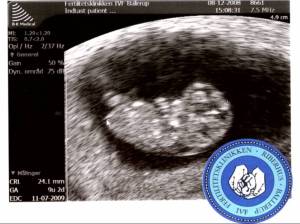

I går var vi til scanning igen – alt ser helt fint ud. Barn’is lå og spjættede – og det lille bitte hjerte slog lystigt! Åh, det var bare helt fantastisk! Det lille myr!

Næste scanning bliver nakkefoldsscanningen 29/12. Det er jeg rimelig spændt på.